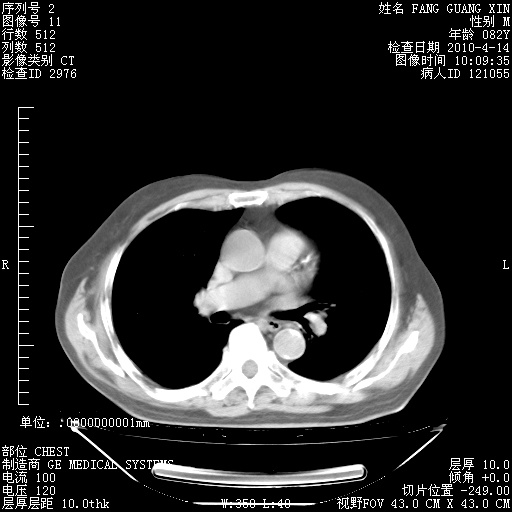

楼主| 发表于 2010-4-28 16:59 | 显示全部楼层

4月28日肺部CT——再次出现类似去年5月9日——透光度降低,(影像科认为)“间质性”改变。

1221483 1 .bmp

1221483 2 .bmp

1221483 3 .bmp

1221483 4 .bmp

1221483 5 .bmp